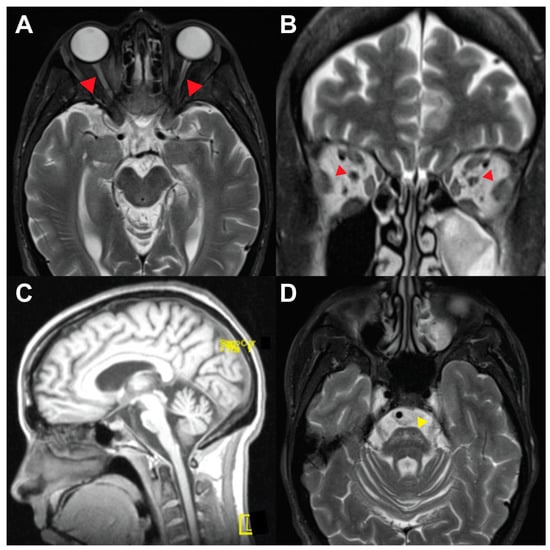

| 4 | 45 | F | c.1230_1233del:p.V412Sfs*29 | Pupillary dilation | 9 | 20s | - | - | Neurogenic bladder | Optic nerve, brainstem, cerebellum atrophy |

| c.1672C>T:p.R558C | Progressive vision loss | Pons T2 hyper intensities | ||||||||